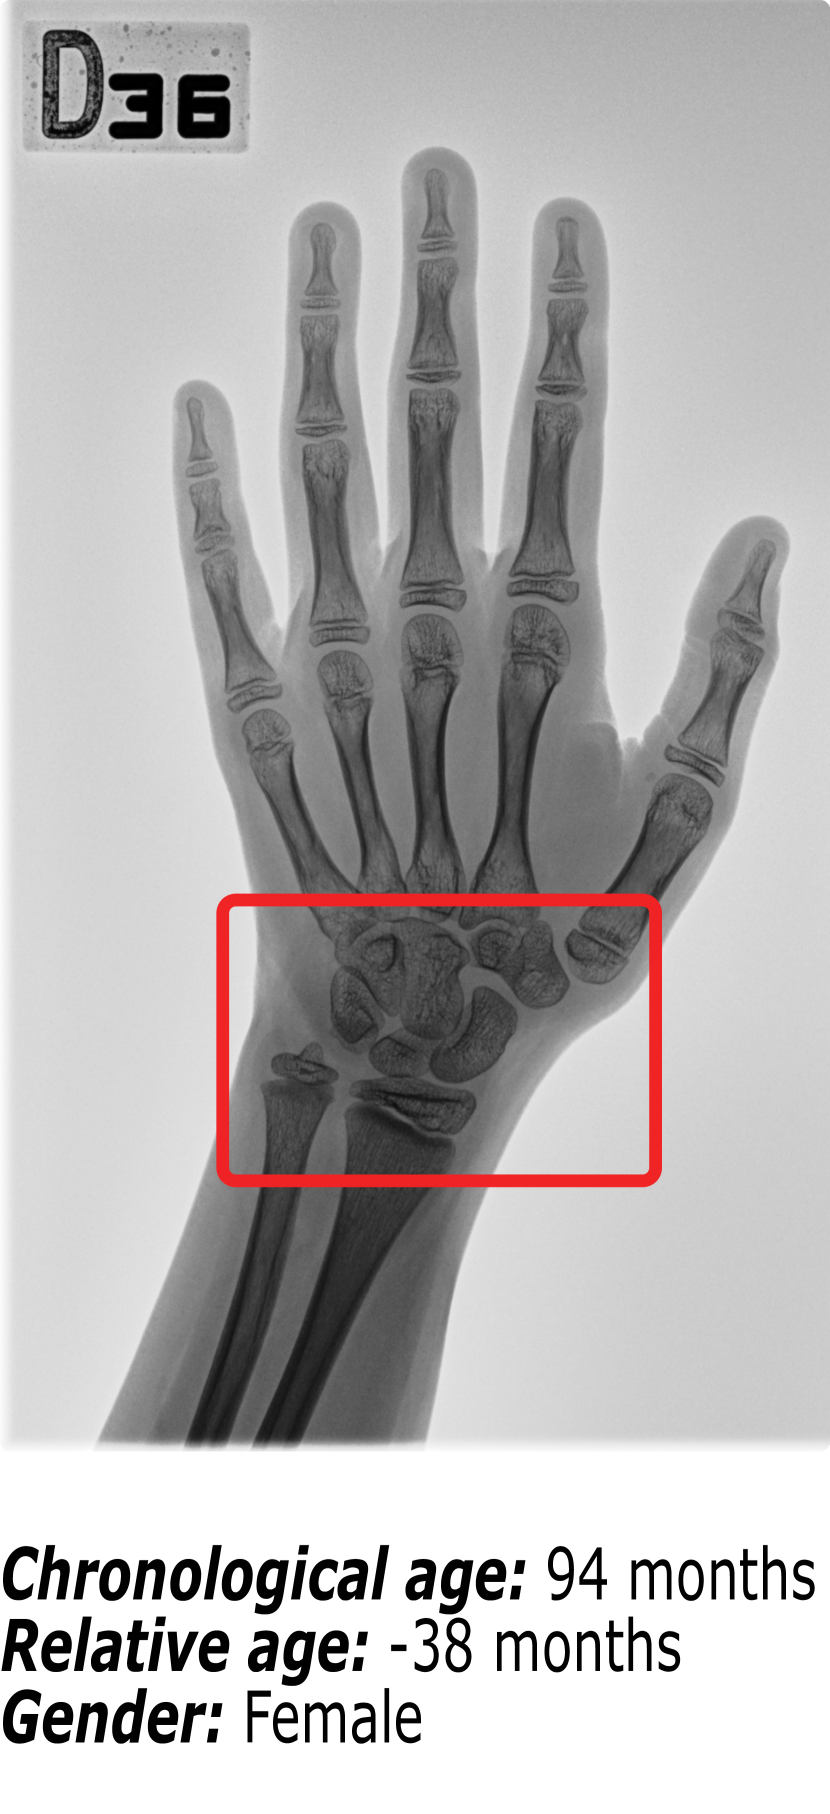

Figure 1 shows an example of the influence that identity markers have on bone age. The three hand radiographs present in Figure 1 belong to children with virtually the same chronological age. However, it is visible that the ossification patterns present in each of the hand radiographs vary significantly. First, gender is an important identity marker to take into account. Comparing Figure 1(b) (a female patient) and Figure 1(c) (a male patient), it is possible to observe that the bone structures in the region surrounded by the red box are more developed for the female than for the male. This finding is supported by the fact that skeletal development is faster in females than in males.

Nonetheless, when comparing two hand radiographs of patients of the same gender with the same chronological age, as it happens between Figure 1(a) and Figure 1(b), the expected result would be that the bone patterns did not vary much. Because most patients have a regular growth pattern, physicians use the chronological age as a starting point and compute the difference in skeletal development. This relative bone age between the patient’s chronological age and the patient’s bone age is the information that the radiologists use to diagnose growth disorders. However, Figure 1(b) belongs to a patient with regular growth, having a relative bone age of +1 month, while Figure 1(a) belongs to a patient with accelerated growth, hence the relative bone age of -38 months.